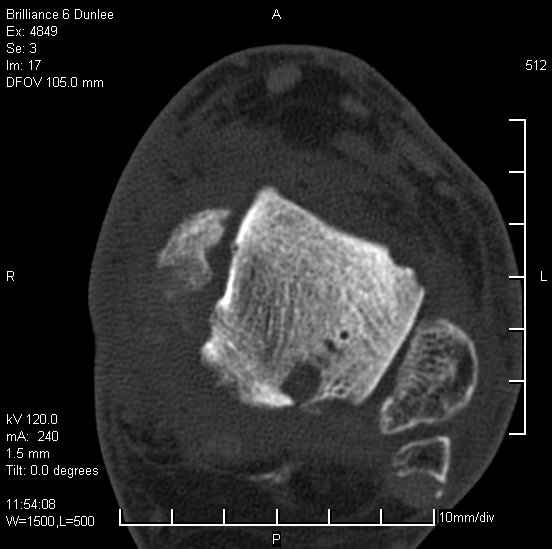

На лечении находится пациент 35 лет. Травма в сентябре 2008 г.- открытый вывих таранной кости

В день травмы ПХО, вправление вывиха, трансартикулярная фиксация. Рана зажила первично. С января нагрузка на конечность. С конца апреля- болевой синдром. На рентгенограммах и КТ признаки ас. некроза таранной кости, артроз подтаранного и голеностопного суставов.